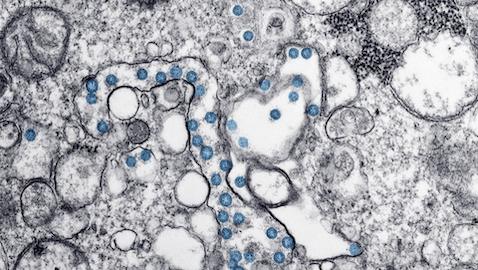

478 × 270